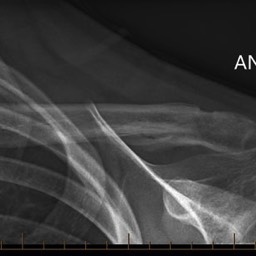

What do clavicle fractures look like on X-ray?

Below are examples of typical fractures that benefit from surgery.

Click an image to enlarge